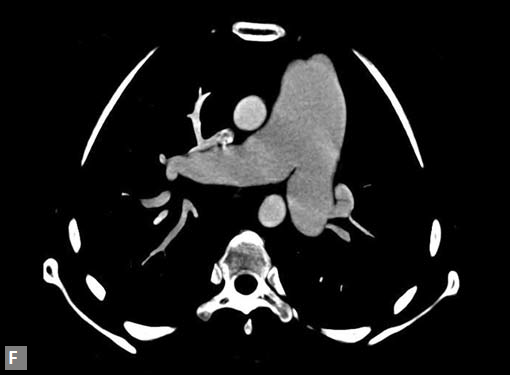

Connective tissue disease, hypertension and iatrogenic (Figs 19K to L) injury are the common causes for dissection. Radiologist not only establishes the diagnosis, also evaluates the extent of dissection, presence of thrombosis particularly in false lumen. In case of type A dissection, involvement of aortic root is determined. Relation of thrombosed lumen and ostia of coronary vessels, cephalad branches (Figs 19N, R to V) of aorta is determined. Most of the occasions membrane is demonstrated. Spiral nature of the membrane can be seen

by evaluating the aorta in all the three orthogonal planes

(Figs 19O to R).

Tennis ball sign is the classical appearance of dissection on

transverse section.

Double barrel appearance is seen on coronal and sagittal

images. Type B dissections can extend even to common

iliac arteries bilaterally. Superiorly it can extend to involve

common carotid and vertebral arteries.

Figs 19A to Y (A to C) Scannogram (A), plain (B) and contrast study (C) show partial anomalous pulmonary venous connection; (D to F) Heterotaxy; (G) Aortic occlusion; (H and I) Aortic stents; (J) Aortic dissection with ‘Benz’ sign due to second dissection within the true lumen; (K, L and M) Aortic dissection with thrombus in pseudolumen following catheter angiogram; (N) Aortic dissection involving common carotid arteries and subclavian artery; (O, P, Q and R) Aortic dissection with right renal artery arising from true lumen and left renal artery from false lumen; (S, T, U and V) Stanford B dissection with extension Y to iliac vessels; (W to Y) Aneurysmal dilation of ascending aorta